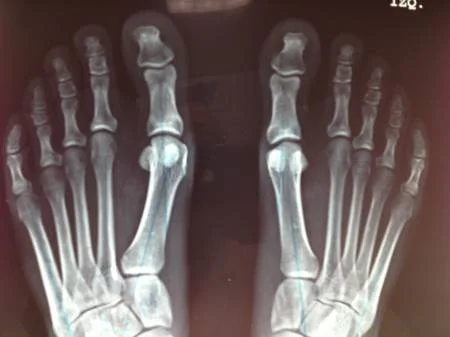

Radiografia preoperatoria

Paciente femenino de 32 años, portadora de hallux valgus doloroso en el pie derecho. Intervenida quirúrgicamente por el Dr Alberto Martínez Conde, practicandole cura operatoria con osteotomia del primer metatarso según técnica de Chevron y fijación con tornillo de Bold de 3.0 mm.